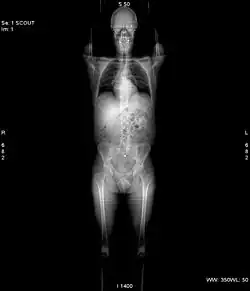

La TC permite estudiar casi todos los órganos internos del cuerpo, desde la cabeza hasta las extremidades, incluyendo los huesos, tejidos blandos, corazón y vasos sanguíneos. La TC es una exploración o prueba radiológica muy útil para el estadiaje o estudio de extensión de los cánceres en especial en la zona craneal, como el cáncer de mama, cáncer de pulmón y cáncer de próstata. Asimismo, la TC es de gran utilidad en los servicios de emergencia, por su gran velocidad de barrido de cuerpo entero, que permite detectar eficazmente fracturas, hemorragias y lesiones de órganos en pocos segundos o minutos. En los últimos años, se ha mejorado su capacidad diagnóstica para el sistema cardiocirculatorio, pudiendo evaluar eficazmente enfermedades agudas y crónicas del corazón y de los vasos sanguíneos.

Las primeras TC se instalaron en España a finales de los años 1970. Los primeros TC servían solamente para estudiar el cráneo, y fue con posteriores generaciones de equipos cuando pudo estudiarse el cuerpo completo. Al principio era una exploración cara y con pocas indicaciones de uso. Actualmente es una exploración de rutina de cualquier hospital, habiéndose abaratado mucho los costos. Con el desarrollo de la TC helicoidal, los cortes son más finos, incluso submilimétricos y la velocidad de barrido mayor. La nuevas TC multicorte incorporan varios anillos de detectores (típicamente entre 16 y 320), lo que permite la adquisición de múltiples cortes simultáneos en cada rotación del tubo de rayos X, lo aumenta aún más la rapidez, logrando imágenes volumétricas en tiempo real.